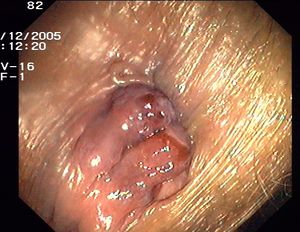

هناك نوعان من البواسير الشرجية داخلية وخارجية.

1- البواسير الداخلية: تنشأ داخل القناة الشرجية في الغشاء المخاطي وهي توسعات وعائية في نهاية الأوعية الباسورية، تتبارز بشكل كتلة صغيرة داخل الشرج، قد تتدلى تدريجياً نحو الأسفل فتصبح البواسير داخلية وخارجية في آن واحد.

2- البواسير الخارجية: وتشاهد عند فوهة الشرج وتكون مغطاة عادة بالجلد، مما يجعلها شديدة الألم وتضم إحدى مجموعتين:

- حادة مؤلمة: وهي بواسير خارجية متخثرة بشكل ورم دموي تحت الجلد يظهر عند فوهة الشرج ويبدو بشكل حبة صغيرة زرقاء اللون شديدة الألم.

- مزمنة: وهي حليمات حارسة جلدية شرجية غير مؤلمة وهي شائعة جداً.

البواسير الداخلية

تظهر أهم أعراض البواسير الداخلية [2] عند رؤية قطرات أو نقاط دم أحمر متقطعة عند عملة التغوط (التبرز)، والمشكلة هنا هي أن الدم يظهر في أغلب الأحيان دون شعور المريض بالألم، ولهذا السبب غالباً يتعرف مريض البواسير الداخلية[3] علي مرضه في وقت متأخر من الإصابة بحيث تكون البواسير ممتلئة بالدم وتكون جلطة، أو في بعض حالات البواسير الداخلية عندما تكون البواسير قريبة من فتحة الشرج.